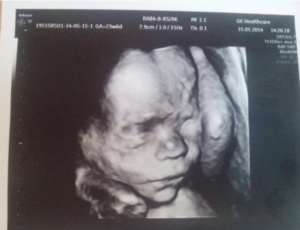

Лицо ребенка полностью сформировано, черты его лица уже отчетливо видно. Волосы закончили свой рост. Пол определен. Обычно к этому УЗИ пол малыша уже известен родителям. На таком сроке врач-сонолог может сделать очень четкое фото после УЗИ.

Идет вторая половина 7-го месяца. Лицо полностью сформировано, на УЗИ можно разглядеть черты лица малютки. Волосы тоже почти выросли. Малыш активно готовится к выходу на свет.

Третье УЗИ на 27-й неделе вынашивания плода позволяет сделать окончательные выводы о протекании столь ответственного этапа в жизни матери и ее ребенка. Во время этого исследования врач дарит мамам фото ее будущего малыша.

В сроке 26-29 недель беременности малыш уже полностью сформирован. Начинает накапливаться подкожный белый жир. Плод уже не такой худенький, формируются милые кожные складочки. Личико малыша уже почти такое, каким оно будет при рождении.

В его чертах угадывается что-то похожее на маму или на папу. Родители могут побаловать себя снимком ещё нерожденного малыша, полученным в процессе ультразвуковой диагностики на этом сроке.